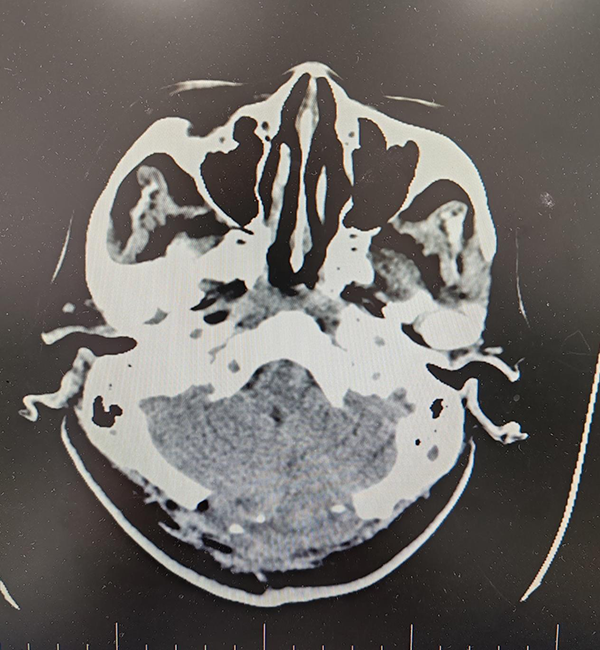

事情追溯到2024年2月7日上午9时许,一名突发意识不清2小时伴有呼吸困难的患者被紧急送入沈阳市第五人民医院急诊室。因为患者曾一度呼吸停止,入院时已携带一枚气管插管,CT检查后发现患者是小脑出血破入脑室,出血量高达30ml,并且已陷入昏迷,没有自主呼吸,急诊室立即给予呼吸机辅助通气,生命危在旦夕。

术前CT提示小脑出血破入脑室 出血量高达30ml